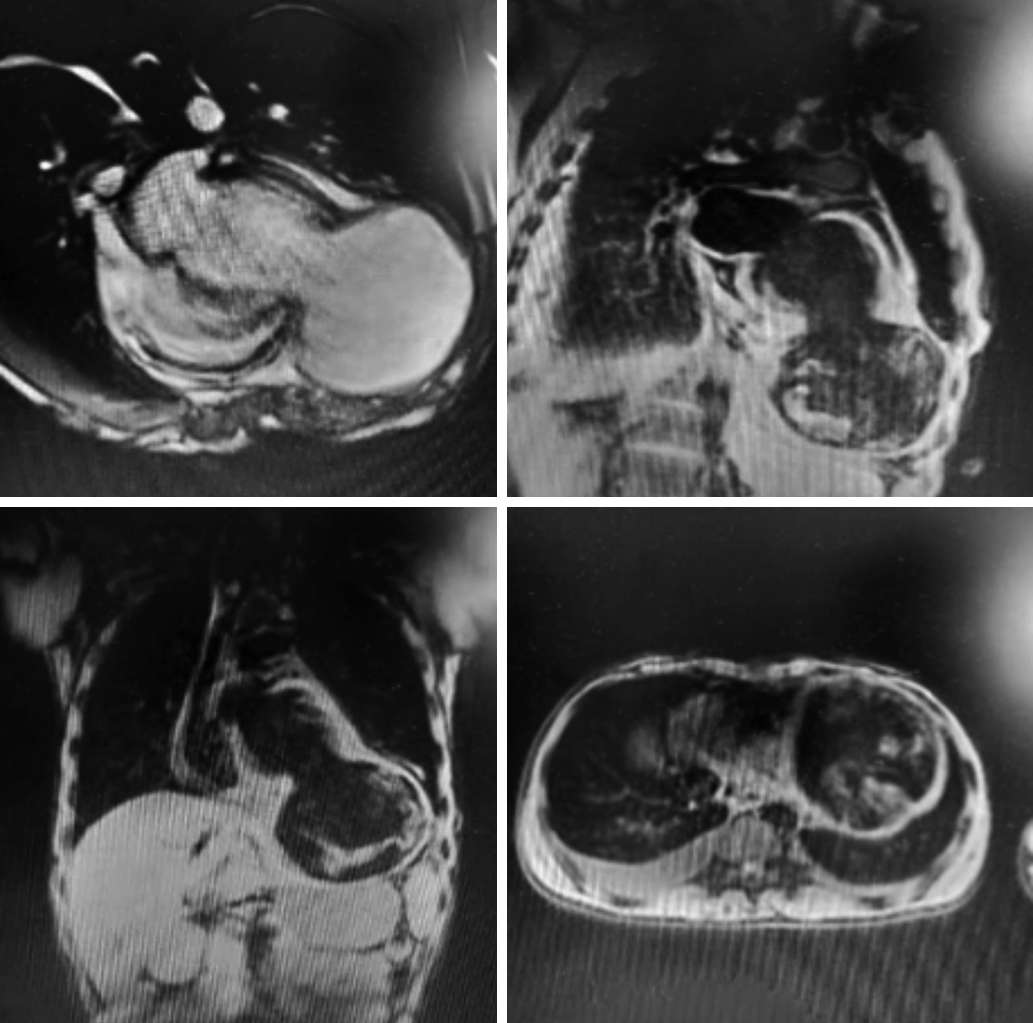

院内胸片检查显示心影明显增大,形态欠规则;两肺纹理增多、模糊,左肺中下野斑片影;左侧膈肌及肋膈角显示不清,不除外左侧胸腔积液(图2)。院内胸部CT平扫检查显示心影增大,左肺中下叶可见多处斑片影,考虑肺水肿以及慢性炎症(图3)。院内心脏MRI检查显示左心室心尖部巨大瘤样膨出;冠状动脉瘤(前降支,多发)结合临床,符合白塞氏所致心脏、冠状动脉改变;肺水肿,心包积液,双侧胸腔积液,考虑心功能不全所致(图4)。